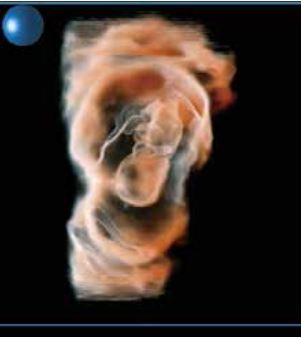

Shadow Glass - це новітня технологія візуалізації, яку можна застосувати до зображень, отриманих за допомогою Smart Sensor 3D. Цей інноваційний метод відображення дозволяє спостерігати внутрішні структури, оскільки він використовує два різні фільтри для створення напівпрозорого об'ємного зображення. У порівнянні зі звичайними 3D-зображеннями, Shadow Glass дозволяє легше спостерігати за цілісними структурами. У випадку плоду Shadow Glass дозволяє чітко роздивитись органи відносно загальної анатомії.

Рисунок 3. Візуалізація плоду з використанням візуалізації об'єму (a), яскравості ( б) та Shadow Glass ( в).